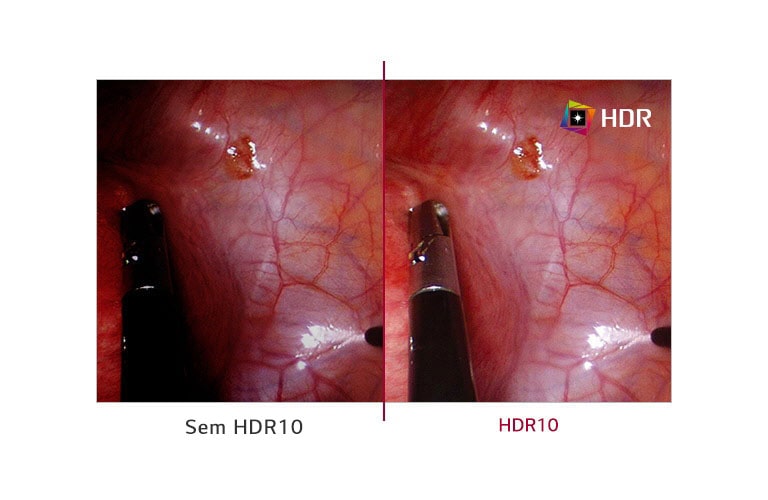

HDR 10

SIM

Efeito HDR

SIM